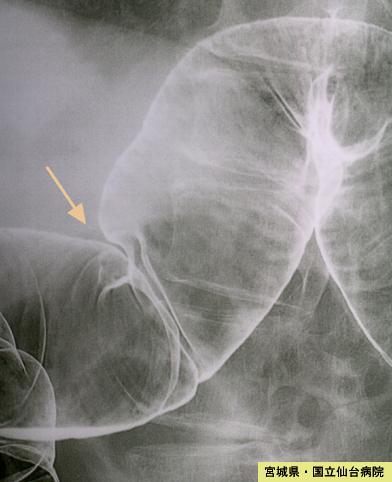

A case of metastatic multiple tumors of the small and large intestine originating from advanced gastric cancer.

Miyagi Pref., Sendai Medical Center (Dr.横田)

[ Image ID:3949 ]

Metastatic tumors/

Location

Large intestine(Colon)/Transverse colon

Technique, Method

X-ray

25 - 29